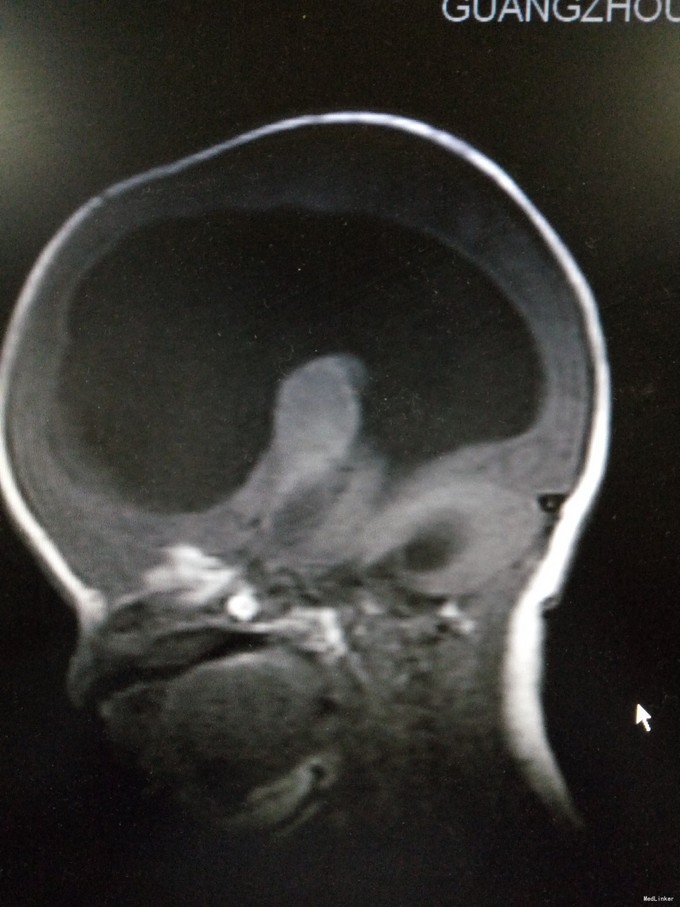

患儿男,29天,因“抽搐1天”入院。患儿足月顺产,出生时无明显异常。其母亲自诉孕期产检无特殊。

查体:发育正常,神清,反应欠佳。前囟3.5*3.5cm,隆起,张力稍高,颅缝分离约0.5cm。双肺呼吸音粗糙,心腹未及明显异常。四肢肌张力稍高,生理反射可引出,病理反射未引出。入院后完善颅脑CT、腰椎穿刺术等,结果如下。

初步诊断为:1.交通性脑积水;2.化脓性脑膜炎。入院后予美罗培南抗感染、营养脑神经、维持内环境平衡等治疗。请神经外科会诊后建议行脑室-腹腔分流术。经近2周治疗后,患儿症状有好转,但病情尚不稳定,家属要求出院,予签字出院。